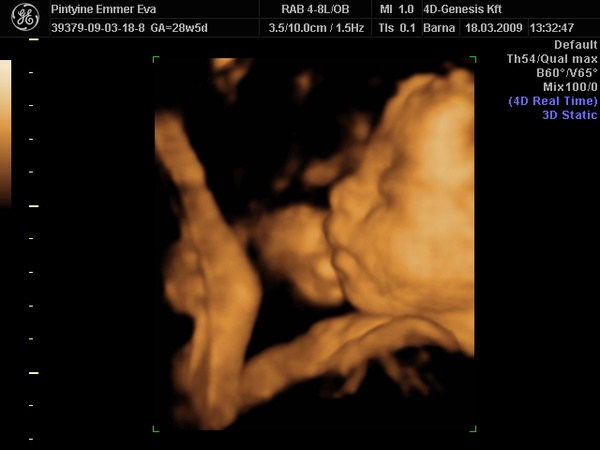

Tegnap pedig voltunk 4D-n a Genesisben. Ismét nem csalódtunk a helyben, és kicsi lányunk rögtön megmutatta, hogy tényleg lány :D Egyik barátnőm kétszer is fiút ingázott, úgyhogy nálunk nem vált be. Szépen mutatta magát, eszméletlenül össze tud gömbölyödni, a térde a fejénél volt, volt hogy a lába volt feljebb a fejénél. Még szerintem van bőven helye megfordulni. A lábikóit mutatta nagyon sokszor. Megszámoltuk a kéz és lábujjait, mindene megvan :D

Méretei:

Súlya: 1204 g

BPD: 71,6 mm

HC: 264,7 mm

AC: 243,6 mm

FL: 51,6 mm

Mensi szerint 28+5 volt tegnap, az uh szerint 28+3.

És egy kép: